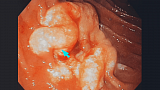

Девушка 1985 года рождения, в анамнезе роды 5 месяцев назад, лактация. ЛХЭ в 2015г. Жалобы на дискомфорт в эпигастрии, вздутие, не температурит. Данное образование в области верхнего дуоденального изгиба, выполнена биопсия, при взятии биопсии, из центра образования, выделилось мутное содержимое в скудном количестве (гной?). Коллеги, ваше мнение. Спасибо.